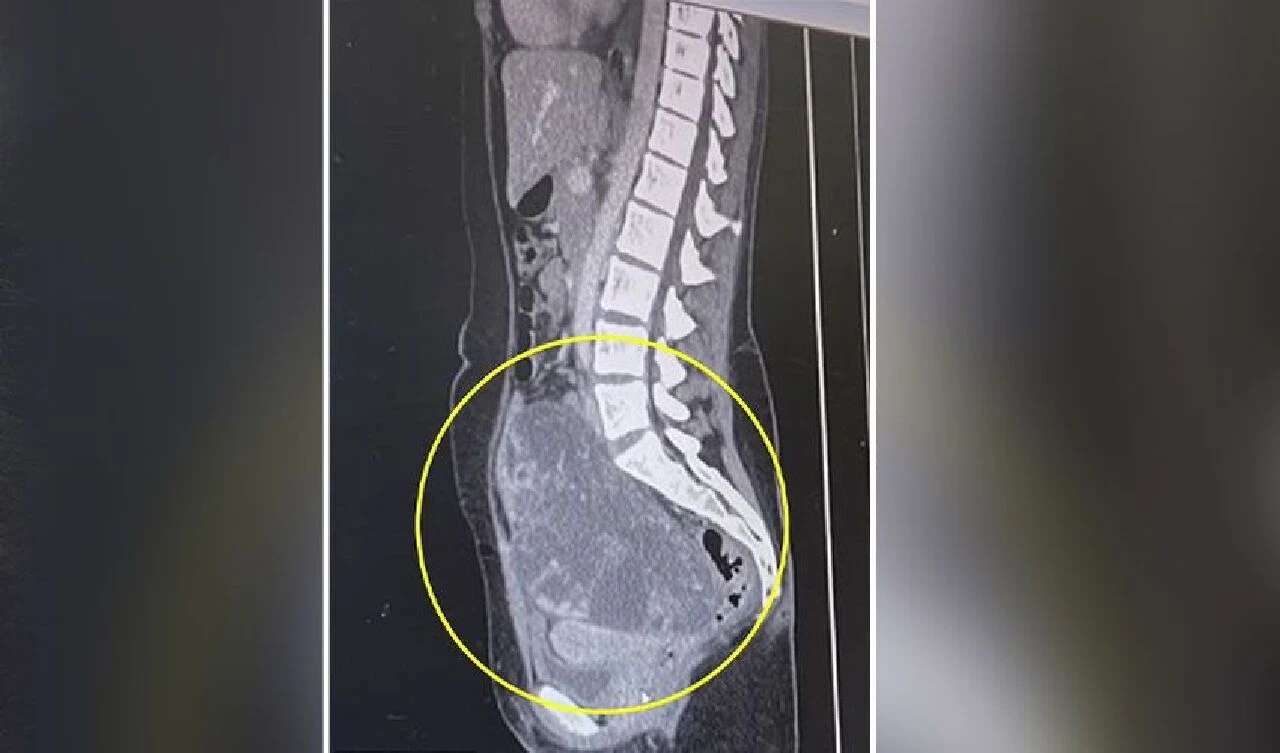

Doktorlar, Robins'e ultrason çektiklerinde yumurtalıklarında, kavun büyüklüğünde, içi saç ve dişlerle dolu bir tümör olduğunu fark ettiler.